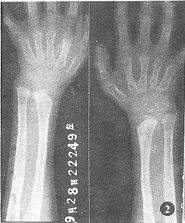

1.2 例2:(例1之妹),女,9岁。其发病过程、临床和X线表现与例1基本相同,唯其尺挠骨、手腕诸骨的表现较为典型(图2)。

图2 双手腕关节正位片:两侧尺挠骨远端变细变形,关节面倾斜分离;

腕骨小而不规则;双侧2~5掌骨近端变尖细,指骨远端呈锥形改变